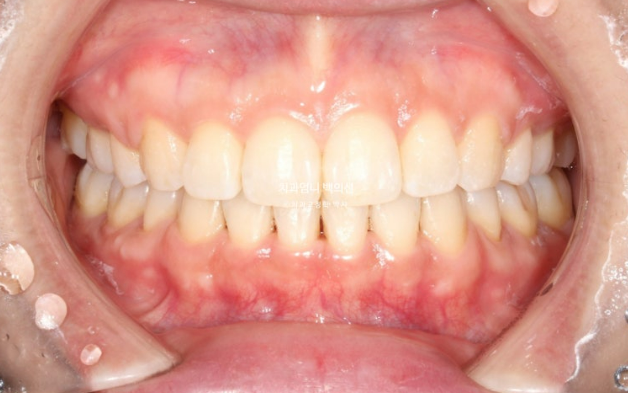

25.04

중심선은 잘 맞고

돌출입 발치교정 입술부전증 치료 후 교합도 좋습니다.